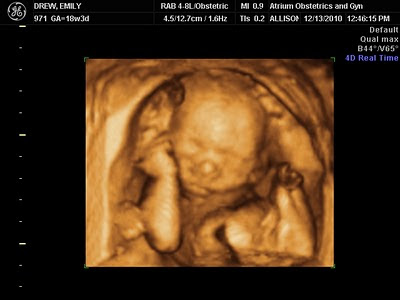

This baby MOVES! I knew SHE did starting around 14 weeks...and she proved her point in the ultrasound today. The ultrasound tech even commented on how feisty this little girl is :) She was constantly moving...and posed very nicely for the tech to get some great pictures.

She looks like a Molly, doesn't she?